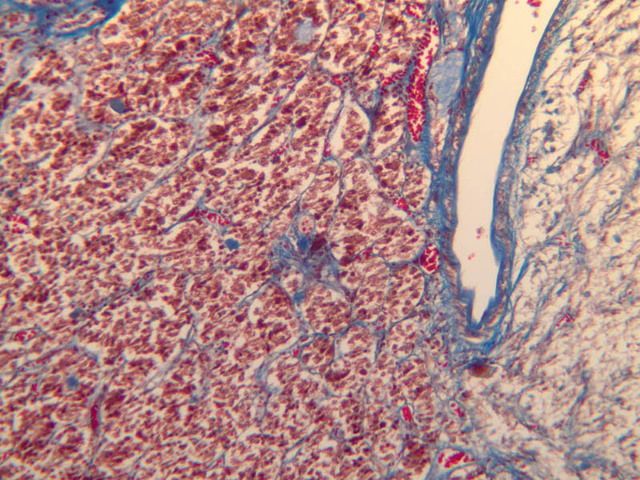

The neurohypophysis arises as an outpocketing of neuroectoderm from the floor of a portion of the brain called diencephalon. It is divisible into the pars nervosa, which forms the posterior portion of the main mass of the pituitary, and the infundibulum, or pituitary stalk. In H&E-stained sections, the neurohypophysis is distinctly eosinophilic. The adenohypophysis (anterior pituitary) has three different types of secretory cells, which are best visualized in the trichrome-stained preparation on slide B-65: (1) acidophils have a reddish staining cytoplasm, owing to the presence of secretory granules. These cells secrete growth hormone (GH) and prolactin (PRL); (2) basophils are slightly larger cells with bluish staining granules present in the cytoplasm. These cells tend to occur in small groups or clusters. Basophils are responsible for the production of thyroid stimulating hormone (TSH), adrenocorticotrophic hormone (ACTH), and the gonadotrophic hormones follicle stimulating hormone (FSH) and luteinizing hormone (LH ); (3) chromophobes or C cells are smaller cells and have only a small amount of poorly staining cytoplasm (B-63, H&E [2.5x-labeled, 10x, 20x, 40x-labeled] [2.5x, 10x, 20x, 40x-labeled]; B-65, trichrome [2.5x, 10x, 20x, 40x-labeled] [2.5x, 10x, 20x, 40x] [10x, 20x, 40x-labeled] [2.5x, 10x, 20x, 40x] [2.5x, 10x, 20x, 40x]). What is the target organ of each of the hormones produced by the adenohypophysis? Note the rich vascularity of the adenohypophysis. Can you describe the blood supply and its significance?

The adrenal gland (slide B-59, H&E [2.5x-labeled, 10x-labeled, 20x, 40x-labeled] [2.5x, 10x-labeled, 20x, 40x]; B-60, H&E [2.5x-labeled, 10x, 20x, 40x]; B-62, H&E [10x, 20x, 40x] [2.5x, 10x]) is a composite organ consisting of two functionally, structurally and embryologically different parts—an outer cortex and an inner medulla. Observe the gland at low power. Find the loosely organized tissue that comprises the medulla and the partially-separated columns of cells that make up the cortex. Scan the capsule and the tissue around it, looking for nerves and blood vessels. Study the pattern of cortical vasculature. In a pattern similar to that seen in the pars distalis of the pituitary, sinusoids run along the edges of columns or cords of cells. Owing to different arrangements of its constituent cells, the adrenal cortex has a layered appearance. From the capsule inward, these cortical layers are known as the zona glomerulosa, the zona fasciculata, and the zona reticularis.

The zona glomerulosa is located immediately beneath the capsule (B-60 adrenal gland, dog [10x, 20x] [20x, 40x]; B-59 [2.5x, 10x, 20x] [2.5x, 10x, 20x]). Its constituent cells are arranged in arcs or spheres, and, owing to their relatively small size, their nuclei appear to be close together. Cells of the zona glomerulosa secrete mineralocorticoids (e.g., aldosterone). The zona fasciculata consists of parallel columns or cords of cells that radiate toward the medulla and are separated by blood sinusoids (B-60 [2.5x, 10x, 20x, 40x]; B-62 [20x, 40x]). Owing to the extraction of lipids during histological processing, the cytoplasm of cells in the zona fasciculata appears highly vacuolated or "foamy". Cells of the zona fasciculata secrete glucocorticoids (e.g., hydrocortisone & cortisone) and some gonadocorticoids (weak androgens). The zona reticularis is the deepest cortical layer and lies adjacent to the medulla (B-60 [20x, 40x]; B-62 [20x, 40x]). It is characterized by irregular, interconnecting cords of cells which are separated by anastomosing capillary networks or sinusoids. Cells of the zona reticularis, which are smaller than those of zona fasciculata and do not contain as many lipid vacuoles, secrete gonadocorticoids and some glucocorticoids.